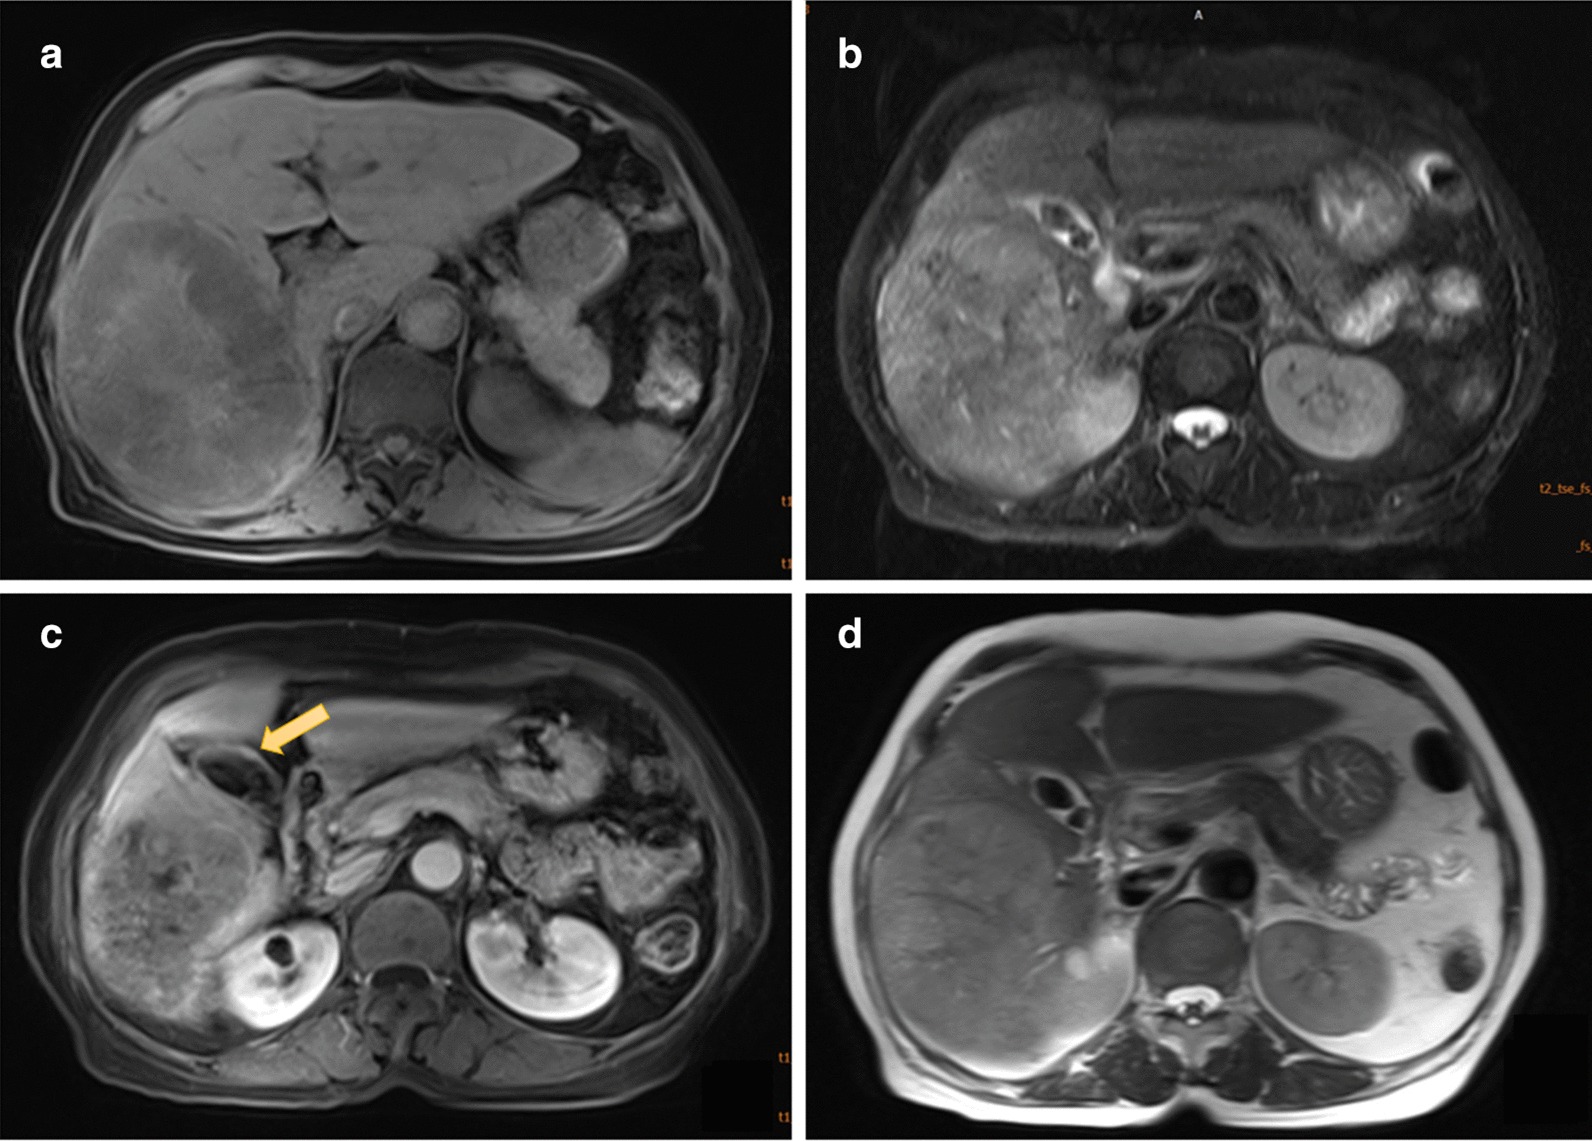

In 2017, a 77-year-old retired female patient was admitted to our hospital, which serves as an outpatient hospital, with only complaints of weakness and inappetence for 6 months. A contrast-enhanced CT indicated an 11 cm space-occupying lesion in the right lobe of the liver. There was no particular family history or infectious medical history. She did not receive any medical intervention before admission, and her vital signs, such as blood pressure, heart rate, respiration rate and body temperature, were normal. Physical examination showed the appearance of mild cachexia, no significant abdominal symptoms such as tenderness, rebound tenderness or muscular tension were noticed, and the abdomen was soft. Palpation revealed a normal liver and spleen, and normal borborygmus existed. The blood routine was normal, other blood chemistries showed a serum albumin of 29.3 (40–55 g/L), ALT of 21 (< 15U/L), AST of 98 (13-35U/L), T-Bil of 17.7 (5.1–20.5 µmol/L), CEA of 3.02 (< 4.7 ng/mL), CA19-9 of 7.49 (< 39U/mL) and CA12-5 of 20.35 (< 35U/mL), but a unusually high level of AFP (more than 1210 ng/mL). Serological tests for hepatitis viruses B and C were negative, as were other infectious indications. Then, the patient underwent an MRI examination that revealed a suspicion of a massive hepatoma (8.9 × 12.3 × 9.9 cm) and multiple gallstones. In fact, there was slight local nodular thickening in the gallbladder wall that was easily ignored (Fig. 1).

Fig. 1.

Abdominal MRI showed an 8.9 × 12.3 cm-sized mass, gallstones and slightly local nodular thickening in the gallbladder wall; a and c T1W images, b and d T2W images